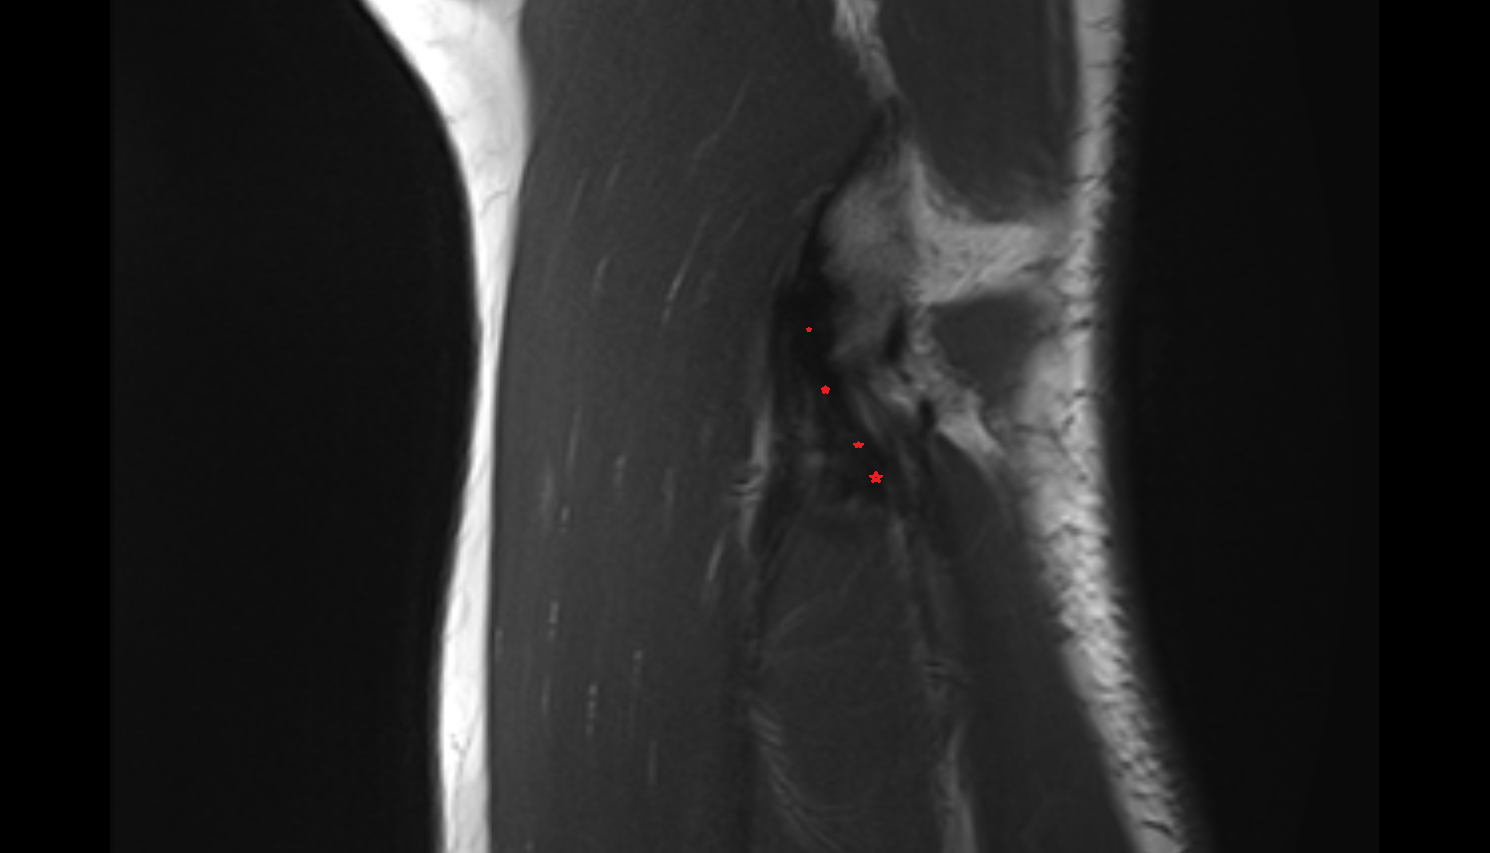

- Anterior cruciate ligament

- Posterior cruciate ligament